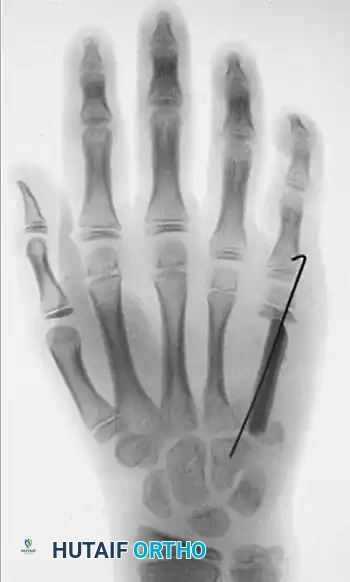

Preoperative radiograph demonstrating an eccentric, expansile enchondroma of the proximal phalanx.

Postoperative radiograph following thorough intralesional curettage and dense packing with cancellous bone graft.